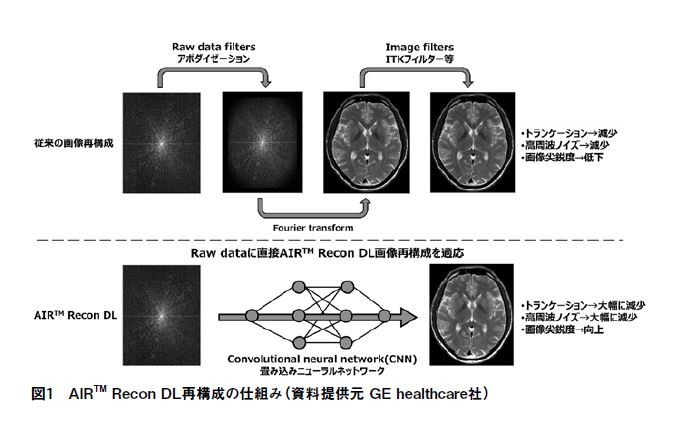

AIR™ Recon DLの特長として主に①ノイズの劇的な低減によるsignal-to-noise ratio(SNR)の向上、②空間分解能の向上、③トランケーションアーチファクトの低減が挙げられる。これまでの様々な高速化技術やフィルター処理等の経験則から、「ノイズ低減によるSNR向上技術」と聞くとSNRの向上に反して、空間分解能の低下やコントラストの低下が生じるのではないか?と疑いを持つかもしれない。しかし、AIR™ Recon DLを使用することによる上記のような懸念は無く、SNRの高い、非常に鮮明なMR画像を得ることが可能である。AIR™ Recon DL再構成は従来再構成のようにフーリエ変換を介さず、raw dataから直接畳み込みニューラルネットワークを介して、MR画像を再構成する(図1)。現仕様では、2D撮像のみの対応となっており、DL再構成によるdenoising levelはLow、Medium、Highの3段階で調整可能である。また、比較のためにDL再構成処理なしのoriginal画像も出力可能となっている(図2)。再構成に費やす時間も従来再構成と比較して遜色なく、「画像がなかなか出てこない!」といったようなストレスを感じることなく業務を遂行できる。